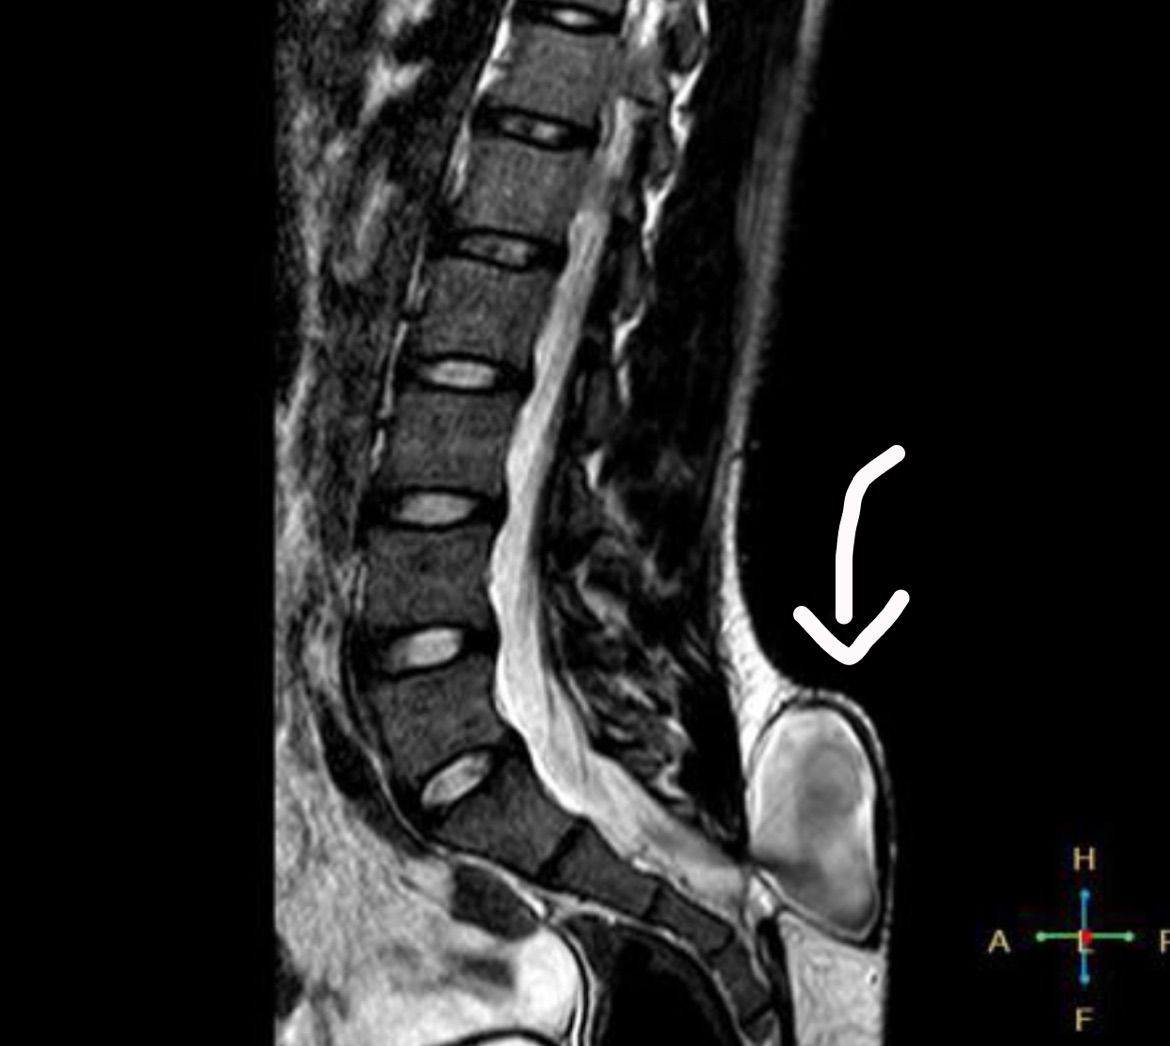

MRI depicts a relatively large case of what was diagnosed to be myelomeningocele. Early on during the development of the fetus, the ectoderm (outmost later of a fertilized egg) begins to form a ridge which will later become the neural tube. However, in spina bifida patients, this neural tube does not close properly. As a result, usually in the lumbar or sacral regions, there is an absence of a vertebral arch (composed of the spinous process, transverse process, pedicles, lamina, and the articular process). There are different forms of spina bifida for which myelomeningocele is the most severe as the spinal cord and the surrounding meninges (dura, arachnoid, pia) protrudes out of the vertebral body. Myelomeningocele is usually seen in Arnold Chiari II Malformation for which findings include obstructive hydrocephalus, myelomeningocele, corpus callosum dysgenesis, no septum pellucidum, sometimes extended cerebellum tonsils into the foramen magnum, small posterior fossa, etc. It is known that a Vitamin B9 deficiency during the development of the fetus is a risk factor for spina bifida. Now, as for diagnosis of spina bifida, one must look for elevated alpha fetoprotein. Furthermore, as with ordered blood tests, one must look for estriol, inhibin A, and human chorionic gonadotropin. All these tests are usually accompanied with an ultrasound.